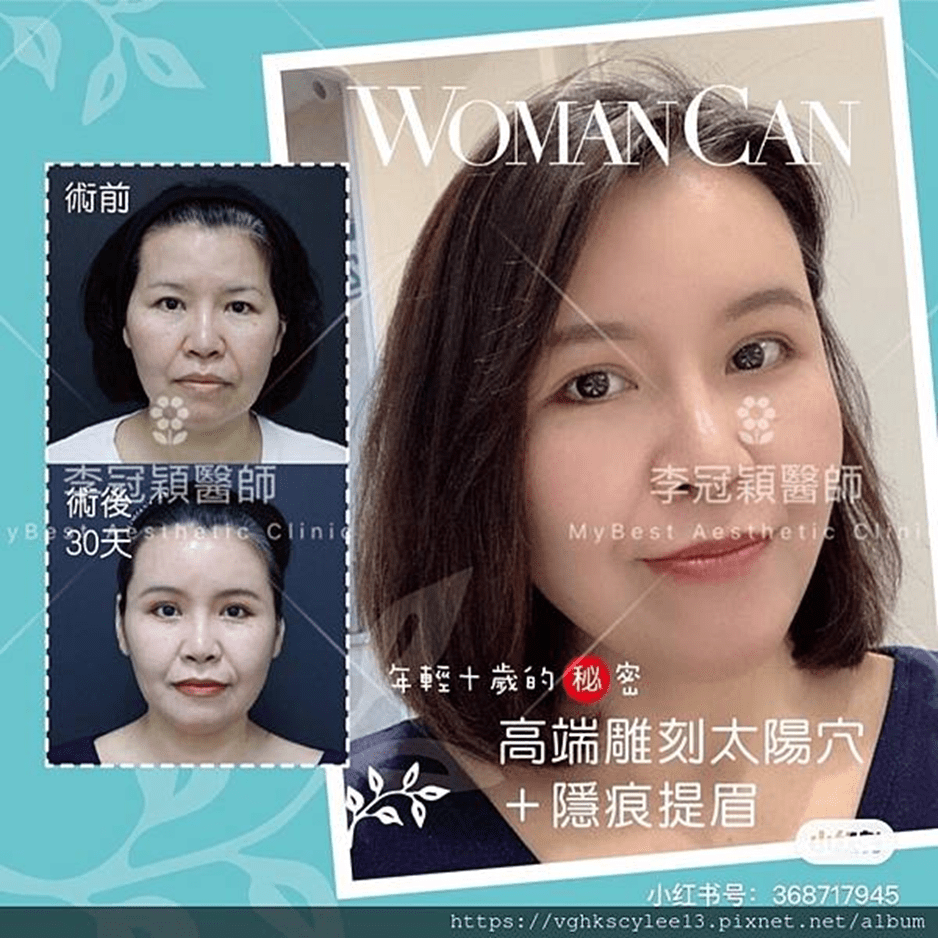

下圖62歲女性:流失凹陷老態,穩定額頭和太陽穴墊片可以改善飽滿度提升年輕外觀。避免全臉填充風險副作用。

(下圖)凹陷太陽穴,提前老態與眼尾下垂,經李醫師內視鏡太陽穴墊片支撐眼尾,幾乎不鬆垂完全抗老。

(下圖)內視鏡提眉與太陽穴墊片(相同入口)可一次性完成的無痕跡年輕化,同時改善臉骨過大比例與不對稱。